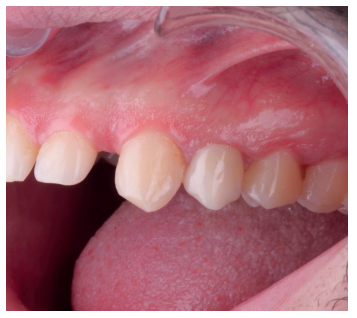

Una vez se hubo posicionado el diente 2 mm supragingival, se procedió a la ferulización con alambre de acero a los dientes adyacentes (Figuras 3 y 4) y la eliminación de cualquier tipo de oclusión, utilizando topes oclusales en los segundos molares inferiores. La ferulización se mantuvo durante dos semanas, coincidiendo con el momento de la endodoncia (Figura 5). El paciente fue citado para las revisiones periódicas y posteriormente para la rehabilitación del diente, una vez hubieron concurrido 6 semanas desde la extrusión, en las que se haya obtenido una cicatrización de los tejidos de soporte supracrestales10. En este momento, tras comprobar signos clínicos, periodontales y radiográficos saludables, se citó al paciente para el tallado y la confección mediante flujo digital (Cerec® System) de una endocorona de disilicato de litio (e.max®, Ivoclar Vivadent). El acondicionamiento de la corona se realizó con ácido fluorhídrico y silano, y para la cementación se utilizó cemento de resina (Calibra®, Dentsply Sirona).

adyacentes, tras la extrusión quirúrgica.

la extrusión, tras la endodoncia y retirada de la ferulización.